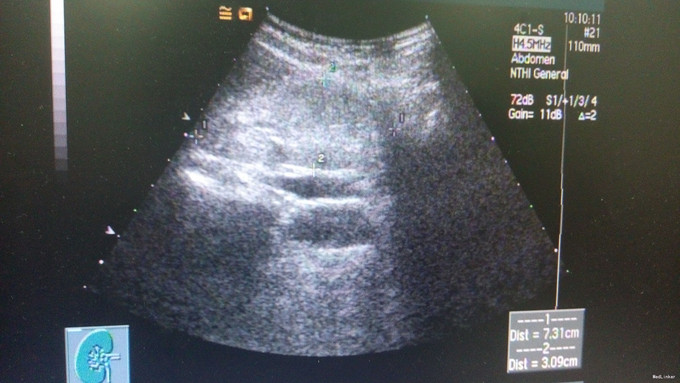

查体:血压135/84mmHg,双下肢可凹性浮肿,眼结膜苍白。 辅查:肌酐924.00umol/L,铁5.7umol/L,总铁结合力30.5umol/L,血红蛋白73g/L,尿素32.13mmol/L,尿酸499umol/L。 肾脏B超显示慢性肾功能不全声像,双肾缩小。对患者进行肾小球滤过率估计:eGFR为4mL/min/1.73mE2。